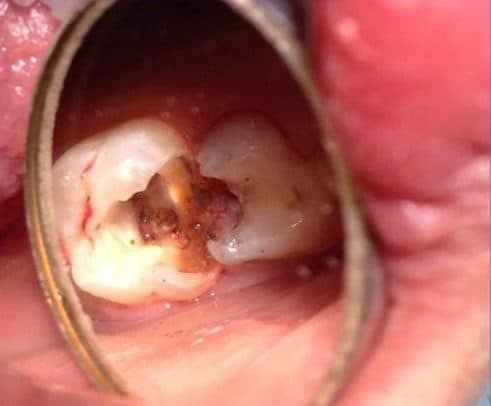

– Tủy răng bị tổn thương: Khi phần bên trong của răng gặp tổn thương do sâu răng, mài mòn hoặc chấn thương, thì điều trị tủy răng trở thành một lựa chọn quan trọng để khôi phục tình trạng răng này.

– Tủy răng bị viêm hoặc nhiễm trùng: Trong trường hợp tủy răng gặp viêm hoặc nhiễm trùng, việc điều trị tủy răng sẽ loại bỏ vi khuẩn và giảm thiểu tình trạng viêm nhiễm, mang lại sự thoải mái cho bạn.

Có một số trường hợp cụ thể cần phài tiến hành điều trị tủy